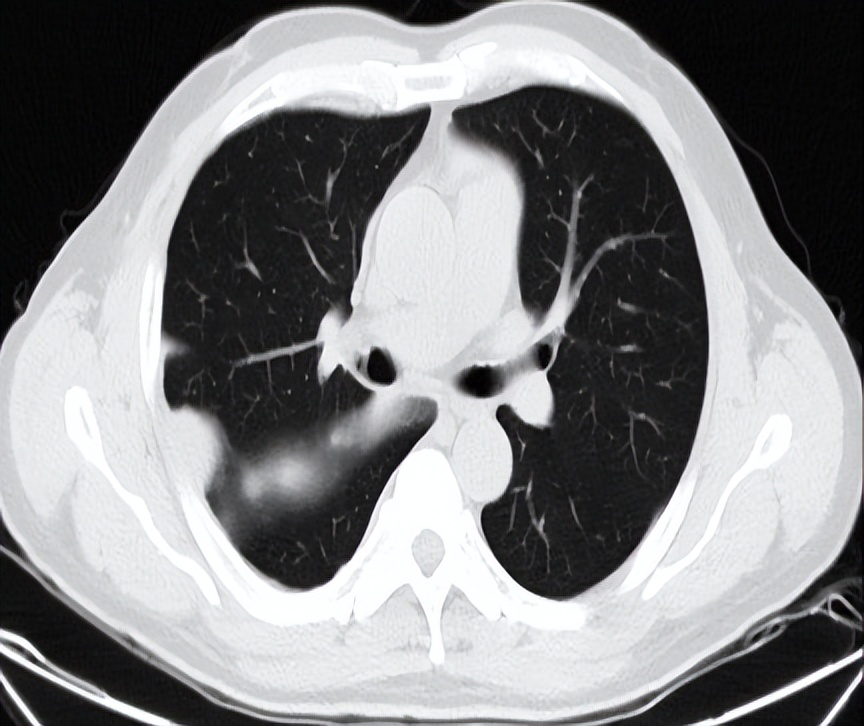

患者男性,56岁,因反复咳嗽入院 2016.12.22行胸部CT检查提示:右侧胸膜为广泛增厚呈不规则状、结节样的增厚,右侧胸腔可见有大量的胸腔积液。纵隔、肺门淋巴结不大,考虑胸膜间皮瘤可能。于2017-1-10行VATS右胸膜活检术,术后病理提示(右胸膜)恶性肿瘤,结合酶标结果考虑恶性间皮瘤。免疫组化结果:TTF-1(-),NapsinA(-),CK7(+),WT-1(+),CK5/6(+),CAL(+),MC(+),D2-40(+)。术后恢复良好,术后予抗炎、补液等对症治疗,诊断为:右侧胸膜间皮瘤cT4N1M0-IIIB期。患者于2017-2至2017-5行AP(培美曲赛联合顺铂)方案化疗共4周期。2017-6-27胸部CT检查提示疗效部分缩小(PR)。